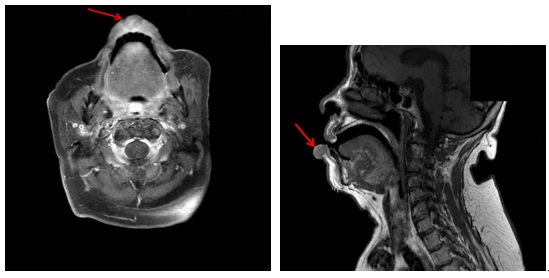

(4) 자기공명영상(magnetic resonance imaging, MRI)

전산화 단층촬영법(CT)과 더불어 임상적 병기 결정을 위한 정보를 얻는데 사용합니다. 연조직에 발생한 암종의 경우 자기공명영상(MRI)이 더 선호되고 있어 구순암 환자의 경우 자기공명영상(MRI)이 필수적이며 신경 외막 침윤 등을 관찰하는데도 유용합니다. 촬영 전 구강 내 보철물은 제거하고 촬영하는 것이 상의 왜곡을 막기 위해 필요합니다.

[아랫입술에 발생한 구순암(화살표)의 자기공명영상(MRI) (T1)]